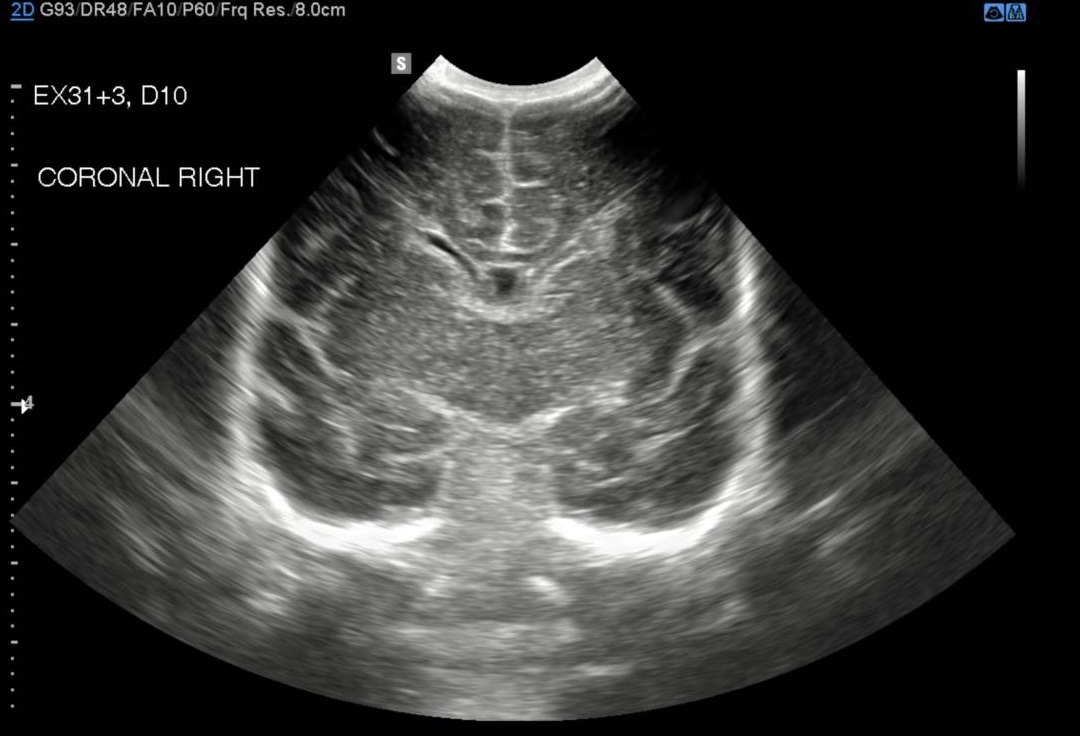

These key documents outline the NICU PoCUS program policy, structure, training and credentialing requirements. The cranial ultrasound images required are 4 coronal and 3 sagittal images.